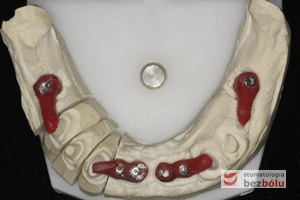

Indywudalizowane filary protetyczne z żywicznymi kluczami - czerwone klucze pattern-resin wyznaczają dokładną pozycję łącznika względem zębów sąsiednich

Indywudalizowane filary protetyczne z żywicznymi kluczami – czerwone klucze pattern-resin wyznaczają dokładną pozycję łącznika względem zębów sąsiednich